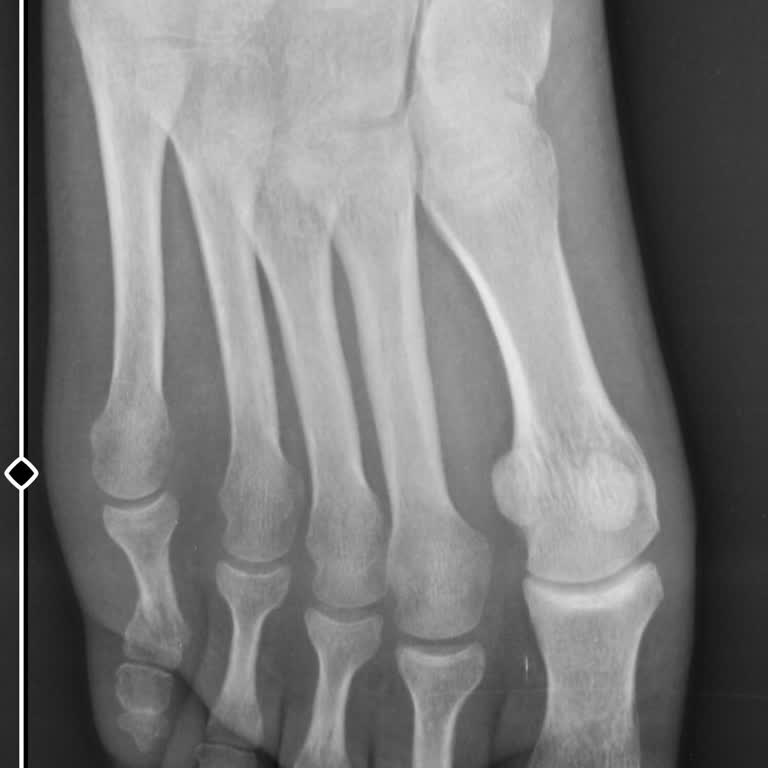

40 gün önce Bigadiç Devlet Hastanesi Ortopedi ve Travmatoloji bölümünde, Dr. H****** B******’a serçe parmağımdaki kırık nedeniyle başvurdum. Muayene sırasında parmağımdaki kırığın 5 derecelik bir açıyla olduğu söylendi ve doktor Elle düzeltme işlemi yapıp alçıya aldı. 2 hafta önce alçım çıkarıldıkta...